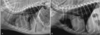

Inspiration vs expiration phases and their affect on thorax xrays.

A

Same animal in both pics.

● Expiration

– Cardiac silhouette appears larger

– Cranial and caudal margin less

defined